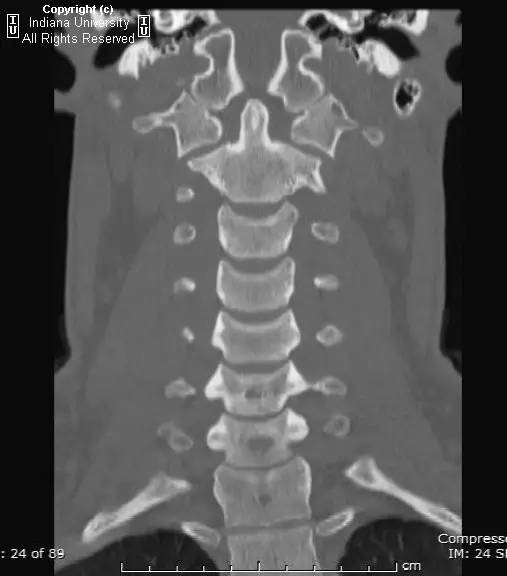

CR: C1侧块相对C2侧块外侧移位约5 – 6 mm,符合Jefferson骨折。椎体周围软组织明显肿胀。MR: 椎体周围间隙可见血肿。覆膜完整。寰枕前韧带断裂。寰枢前韧带完整。左侧横韧带从C1侧块的内侧分离,CT对应在C1侧块内侧见小撕脱骨折。翼状韧带完整。寰枕后韧带完整。前纵韧带和后纵韧带完整。黄韧带完整。

Jefferson骨折(Jefferson fracture)是前后弓均累及的C1环粉碎性骨折。Jefferson骨折为头顶受打击并轴向载荷的结果,力从颅骨经枕骨髁传递到颈椎,C1侧块在枕骨髁和C2上关节面之间被压缩,基于侧块的形状产生向心力而导致C1爆裂骨折。齿状突开口位或冠状位重建CT图像应仔细观察双侧C1和C2关节侧块间有无偏移。虽然C1侧块相对C2上关节面侧方移位提示存在骨折,但在X线片上有时难以发现骨折线。MR可显示相应的韧带损伤。

Jefferson骨折。A,侧位片示C1后弓骨折线(箭)。B,开口位示C1侧块相对于C2偏移(箭)。C和D,轴位CT图像示骨折线通过C1环前、后部(箭)。E,冠状位CT图像示翼状韧带小的撕脱骨折(黑箭)。此图像上也标注了C1在C2上方偏移(白箭)。